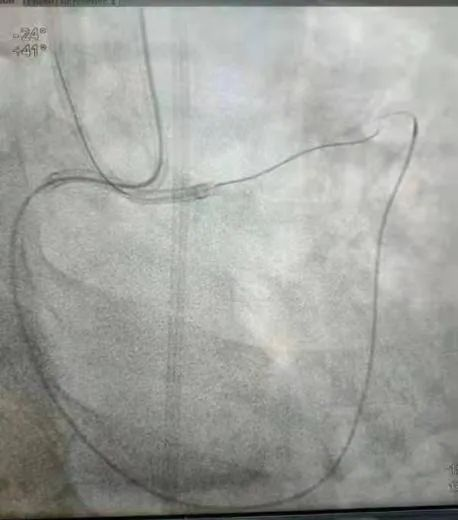

逆向导丝通过病变进入正向指引导管

术中,何鹏程教授细致阅读对侧造影影像,在密密麻麻细小的侧支血管中,快速精准选择好合适的侧支入路,导丝逆向通过慢性闭塞病变顺利送达正向指引导管,成功开通闭塞血管。经冠状动脉介入术后次日,患者病情稳定办理出院。